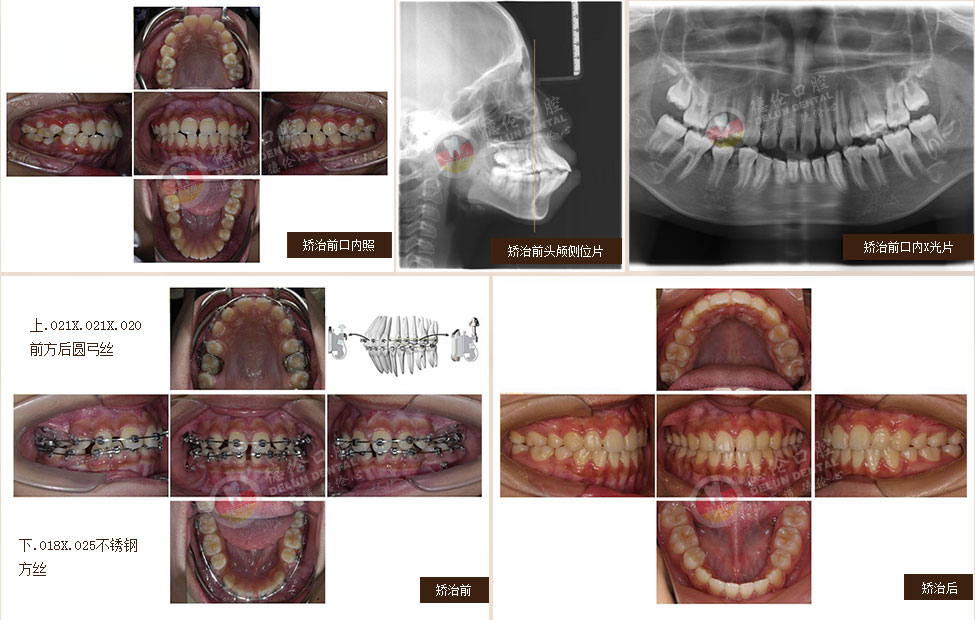

• 女:13歲

癥狀:上下前牙前突、唇傾,上下牙弓散在間隙

矯治方法:SPEED矯治器結(jié)合種植釘、整體內(nèi)收上下牙弓、改善雙牙弓前突以及凸面型側(cè)貌

• 男:17歲

癥狀:下頜右側(cè)第二、第三磨牙水平阻生,下頜左側(cè)第三磨牙水平阻生

矯治方法:下頜拔除兩顆第三磨牙(智慧齒)

• 女:19歲

癥狀:上下前牙前突(雙牙弓前突)

矯治方法:SPEED自鎖矯治器治療 拔除上下第一雙尖牙、排齊上下牙列、內(nèi)收上下牙弓,改善面部側(cè)貌。

• 女:24歲

癥狀:牙列不齊、下頜第二、第三磨牙水平阻生,左側(cè)磨牙鎖牙合

矯治方法:拔除上頜及右下第一雙尖牙,左下第二雙尖牙以及2個下第三磨牙